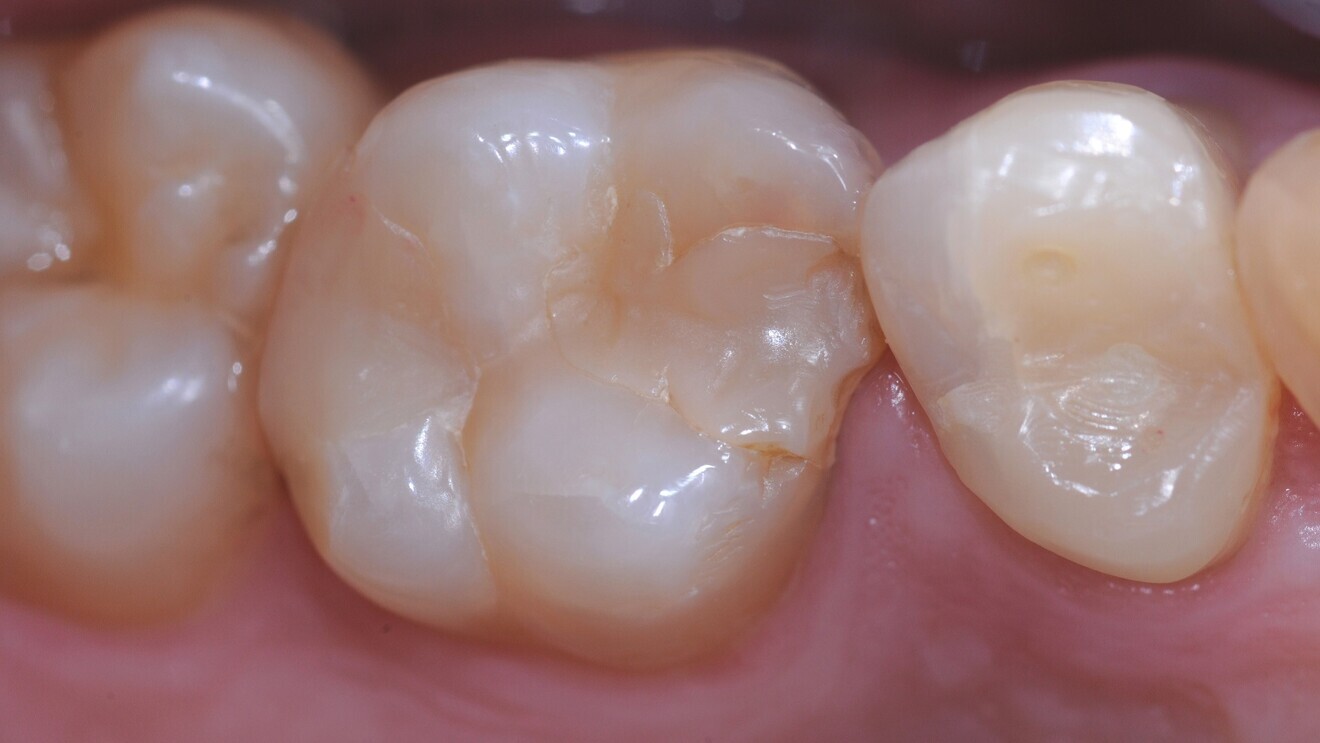

Fig. 2: Cervical lesions restored with the glass hybrid EQUIA Forte.

The first study included a small sample of 25 patients with non-carious cervical lesions and bruxism.6 In these overall rather young patients, 148 lesions were randomly restored, indicating a massive clustering of the lesions per patient, with either a glass hybrid (EQUIA Forte, GC) or a resin composite (ceram.x one universal, Dentsply Sirona). After six, 12 and 24 months of follow-up, the restorations were re-evaluated using the modified United States Public Health Service (USPHS) criteria. When assessing the 126 remaining restorations in 22 patients at the 24-month recall, it was apparent that both materials had performed similarly. Only for marginal adaptation was a significant difference found, the glass hybrid showing slightly reduced adaptation. Secondary caries was not observed on any of the restorations.

Another study, with a follow-up of 36 months, assessed the survival, quality and costs of glass hybrid (EQUIA Forte) and resin composite restorations (Filtek Supreme XTE, 3M) for managing sclerotic non-carious cervical lesions.7 In 88 patients (50–70 years of age) with 175 lesions, restorations were placed directly without any mechanical preparation, which eventually resulted in high annual failure rates for both groups. Restoration quality was assessed at one, 18 and 36 months using the FDI World Dental Federation criteria. Costs were evaluated using a micro-costing approach (accounting for the time for material placement) and, during follow-up, fee items of the statutory insurance in Germany. Of the 88 patients, 43 received the glass hybrid (83 restorations) and 45 received the resin composite (92 restorations); cluster randomisation had been applied. At 36 months, 17 glass hybrid restorations and 19 resin composite restorations showed total retention loss, and five glass hybrid restorations had been partially lost. There was no significant difference between the materials. The FDI ratings were not significantly different for any domain except surface lustre. Here, the composite restorations were superior to the glass hybrid ones, although it should be noted that the latest generation of glass hybrids address such aesthetic effects. Costs were significantly lower for the glass hybrid restorations—both initially (€32.57; SD: €16.36) and in the long term (€41.72; SD: €25.08)—compared with the resin composite restorations (€51.60; SD: €26.17).